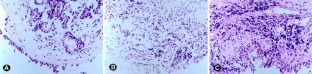

Fig. 1

Fig. 2

Fig. 3